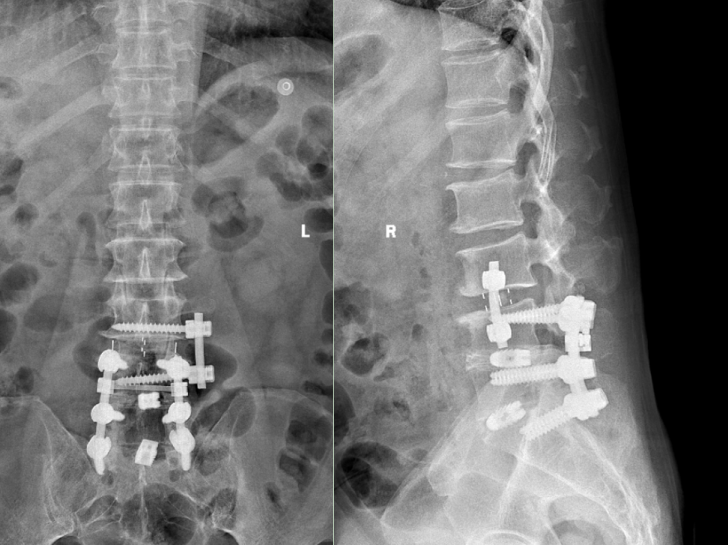

術(shù)后復(fù)查x光片提示腰椎內(nèi)固定位置良好